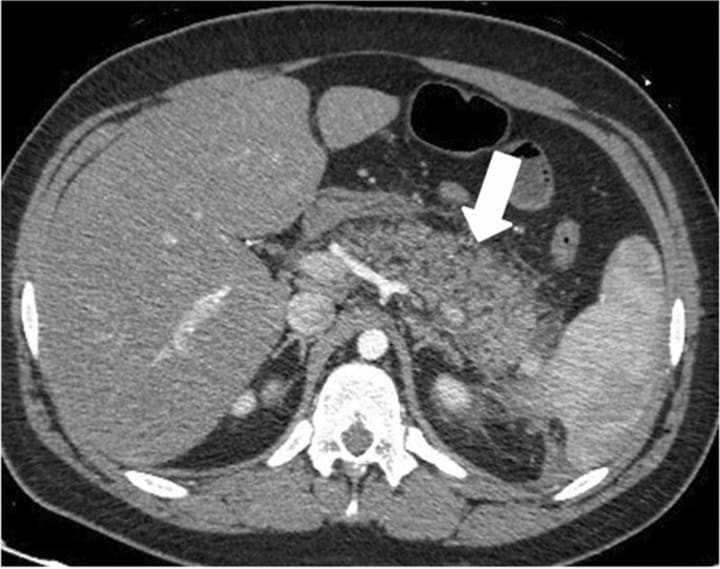

When a patient comes into the emergency room complaining of abdomen pain depending on the the area that they are complaining about, will depend on what the doctor believes the issue can be. Usually the exam that will get done will be a computed tomography of the abdomen. Now depending on the type of pain will depend on wither or not contrast is used. In the case of suspected pancreatitis, contrast will usually be used in these cases.

An intravenous contrasted computed tomography exam of the abdomen, allows the for the vessels and vein to be enhanced. When a patient has suspected pancreatitis using IV contrast with the scan can show and enlarged and or irregular outlined shaped of the pancreas.

When trying to diagnosis pancreatitis it is largely accepted to use IV enhanced CT scan. You can use other imaging modalities however when it comes to keeping up with staging and any possible necrosis and or fluid collections that could happen. It is the most convent and detailed imaging for this type of disease.